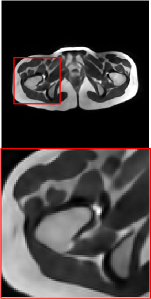

Figure 5 provides the qualitative comparison of the various methods on the four datasets at a scale of 4. The top, second, third, and bottom rows are the SR results under the FastMRI, clinical brain, clinical tumor and clinical pelvic datasets, respectively. The red boxes indicate the zoom-in region of complicated anatomical structures along with their corresponding error maps. Note that the brighter textures in the error maps, the lower the quality of the reconstructed images. As can be seen, compared to methods based on Transformers and CNNs, diffusion-based methods like DisC-Diff and DiffMSR (Ours) are capable of reconstructing high-realistic images with promising reconstruction metric scores (PSNR and SSIM). Nevertheless, while DisC-Diff can reconstruct high-precision MR images, it does not preserve the structure present in the original HR images, introducing some additional information that can affect medical diagnosis. In contrast, our method combines DM and PLWformer, which can preserve the original image’s structure while restoring high-frequency information.

In this section, we present more visual qualitative comparisons. Figures 8, 9, 10, and 11 show the reconstruction results of each method in FastMRI, clinical brain, clinical tumor, and clinical pelvic, respectively. As can be seen, although DisC-Diff can reconstruct MR images with high-frequency information, it fails to preserve the structure and content of the original Target HR image effectively, resulting in image distortion. In contrast, our proposed DiffMSR can restore high-frequency information while preserving the structure of the original HR image, indicating the effectiveness of the joint use of DM and PLWformer.